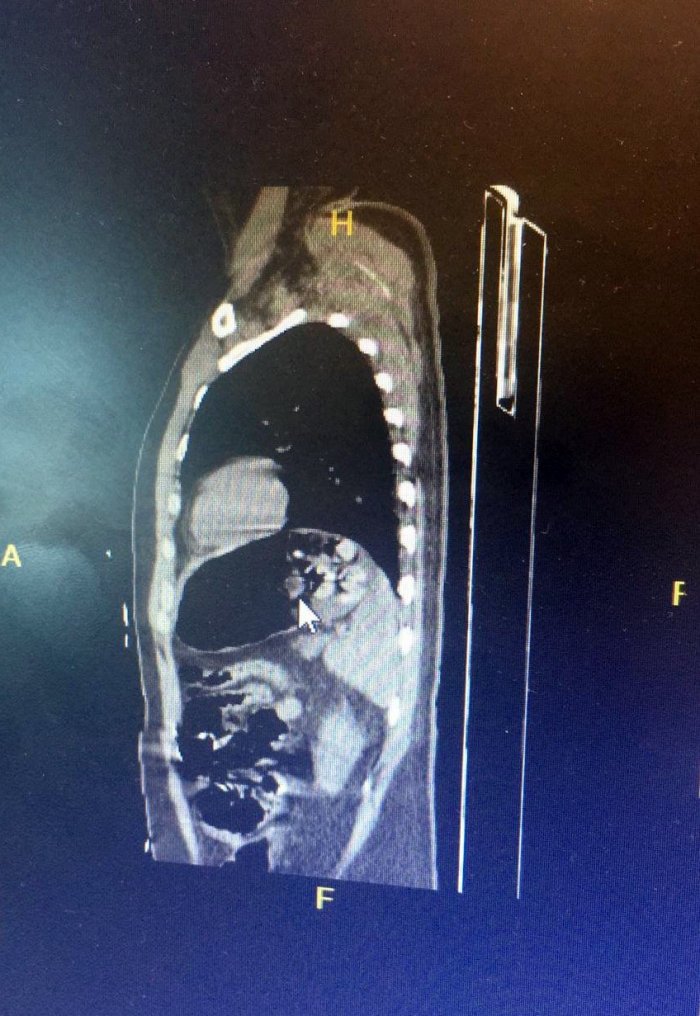

Yapılan çalışmaları neticesinde B.D., gözaltına alınarak emniyete götürüldü. Doğal yollardan midesindeki paketleri çıkartamayan şahıs, rahatsızlanarak hastaneye kaldırıldı. Hastanede ameliyata alınan şahsın midesinden, 2'si patlamış halde olmak üzere 15 paket halinde 192 gram eroin çıkarıldı.